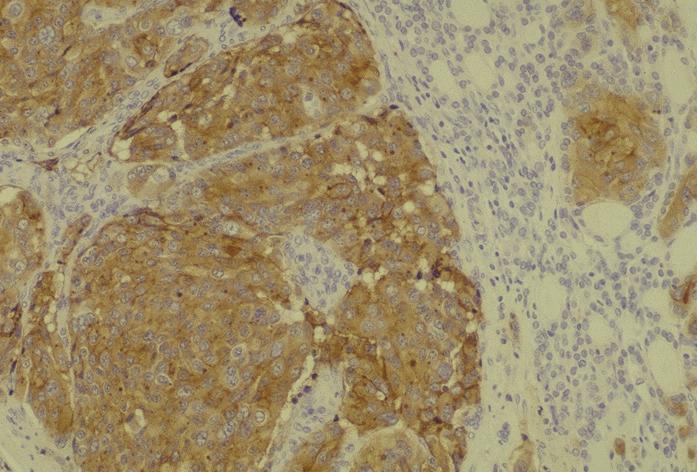

Microscopic (histologic) description

- Wide variety of morphology, can mimic any other thyroid malignancy

- Round, plasmacytoid, polygonal or spindle cells in nests, cords or follicles; often mixtures of these cells

- Round nuclei with finely stippled to coarsely clumped chromatin and indistinct nucleoli, occasional nuclear pseudoinclusion

- Eosinophilic to amphophilic granular cytoplasm due to secretory granules

- Generally low mitotic figures

- Stroma has amyloid deposits from calcitonin, prominent vascularity with glomeruloid configuration or long cords of vessels (Am J Surg Pathol 1995;19:642), coarse calcifications, occasional psammoma-like bodies

- Mucin in 42% (Arch Pathol Lab Med 1983;107:70)

- Often angiolymphatic invasion

- Occasionally marked neutrophilic infiltrate, oncocytic tumor cells, papillary patterns

- May entrap follicles

- C cell hyperplasia present in familial but not sporadic cases

Microscopic (histologic) images

Contributed by Shuanzeng Wei, M.D., Ph.D., Joseph Christopher Castillo, M.D. and Mark R. Wick, M.D.